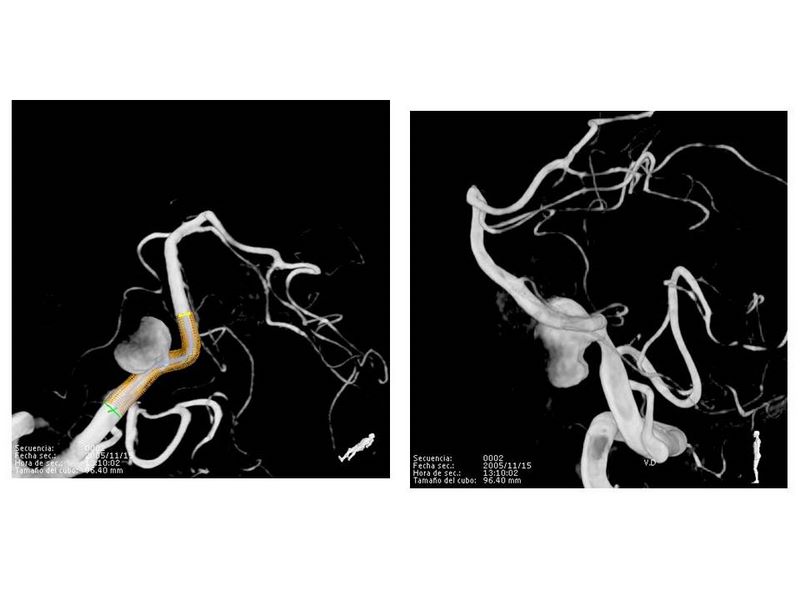

Aneurismas grandes